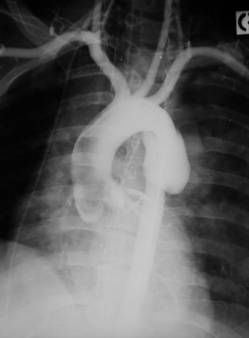

ANEVRISMUL AORTEI

Majoritatea anevrismelor aortei toracice sunt de origine atero-sclerotica si traumatica, restul au cauze micotice, sifilitice si inflamatorii. Aproximativ 25% dintre anevrismele toracice sunt anevrisme disecante ce apar la pacienti varstnici cu hipertensiune si ateroscleroza. Examenul radiologic poate evidentia o opacitate rotunda sau ovalara, de obicei omogena (neomogena cand exista calcificari parietale) net delimitata, intensa, ce nu poate fi separata de opacitatea aortica in nici o incidenta. Radioscopic, aceasta opacitate poate prezenta pulsatii proprii sau transmise de la structurile vecine. In cazul unui anevrism disecant, opacitatea creste rapid in dimensiuni. Imaginea cardiaca este normala, la fel ca si imaginea aortei.

Fig. 35 – Anevrism de aorta descendenta (aortografie)